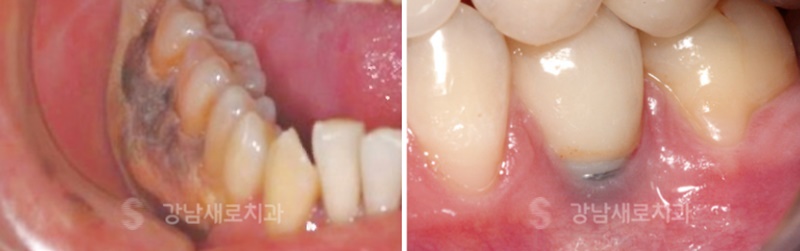

타 치과에서 임플란트 식립 후 재수술을 위해 본원에 내원하셨던

분들의 사진입니다. 왼쪽은 진료 부위에 심각한 염증이

진행중이였고, 오른쪽은 픽스처가 잇몸 밖으로 노출된 사례였습니다.